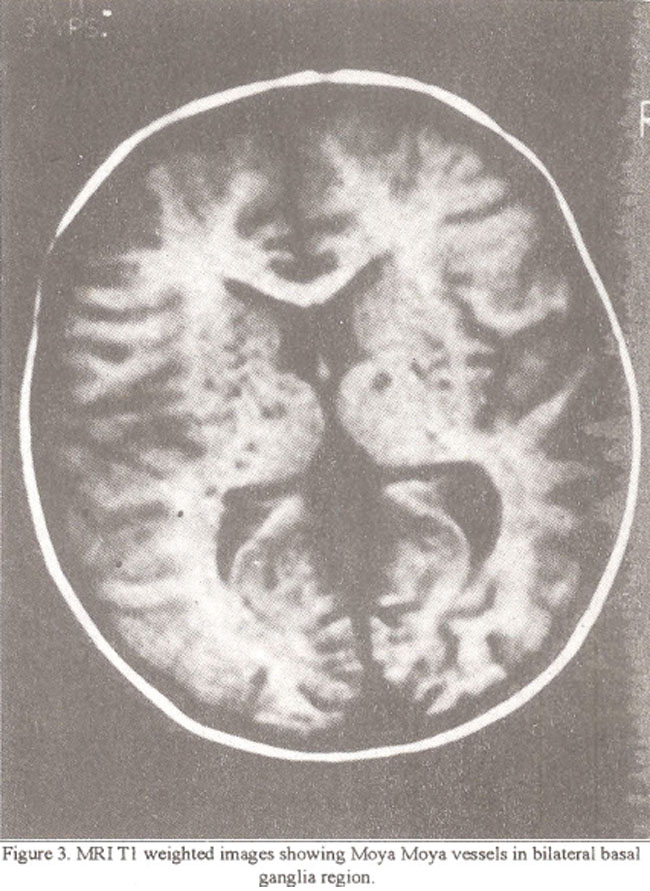

Atrophy and ventricular dilatation was moderate in two patients and mild in one patient. Moya Moya vessels were seen on CT scan only in one patient (Figure 2).

Circle of Willis was not visualized in all three patients who had CT scan. MRJ was able to detect small dilated tortuous signal void areas in the basal ganglia region in three patients (Figure 3).